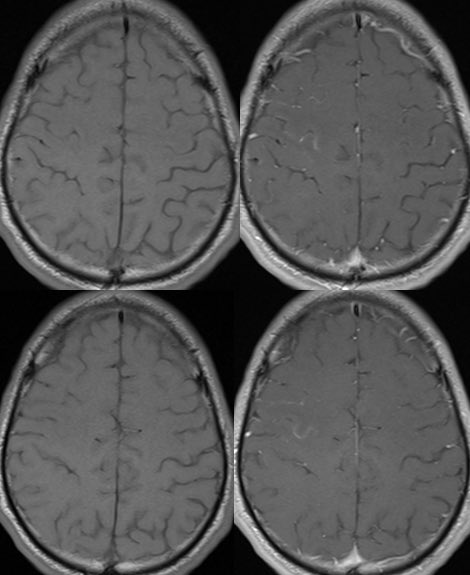

🔷When the predominant imaging features are leptomeningeal enhancement with little to no cortical involvement, this is considered FUEL of MOGAD ⛽️ x.com

🔷FUEL ⛽️& FLAMES 🔥

▶️Imaging: Unilateral (more common) or b/l cortical swelling (🔥) or isolated leptomeningeal enhancement (⛽️) +/- other features of MOGAD

💡 Rule out infection/malignancy first! 🙏 x.com